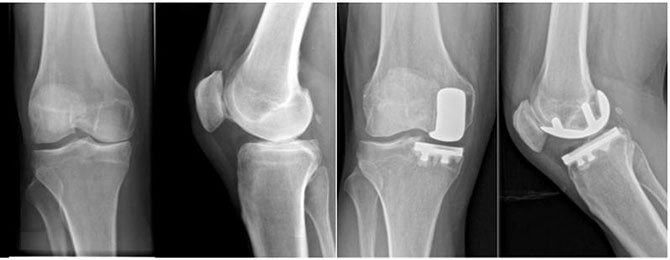

单髁关节置换术,适用于膝关节单纯内侧或单纯外侧间室磨损及下肢力线轻度异常的患者。手术仅针对患侧单间室软骨及软骨下骨进行清理和置换,以改善关节功能,纠正膝关节生物力学轴线,减缓关节进一步退变。具有:手术创伤小、术后康复快、术后功能佳、延后全膝关节置换时机等临床优势。